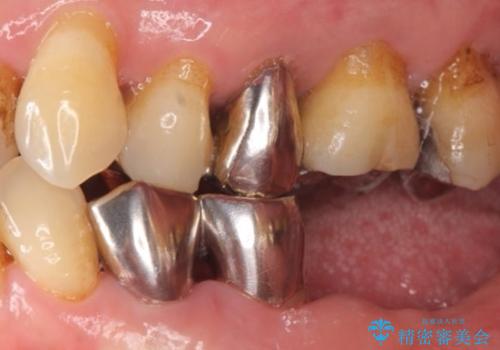

- 下の前歯(左下2)と奥歯の動揺がひどくなってきたことを主訴に来院された患者様です。

精査したところ、前歯の咬み合わせが反対になっていること、下の奥歯(下顎両側67)が4本欠損していることから動揺が生じていました。

入れ歯も抵抗があるとのことから、相談を重ね、今の状態では保存不可能な下の前歯(左下2)を抜去し、ブリッジや連結補綴により動揺を抑えることにしました。